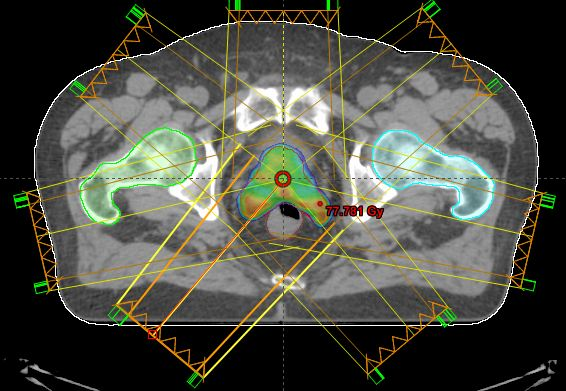

this is a

rotational treatment